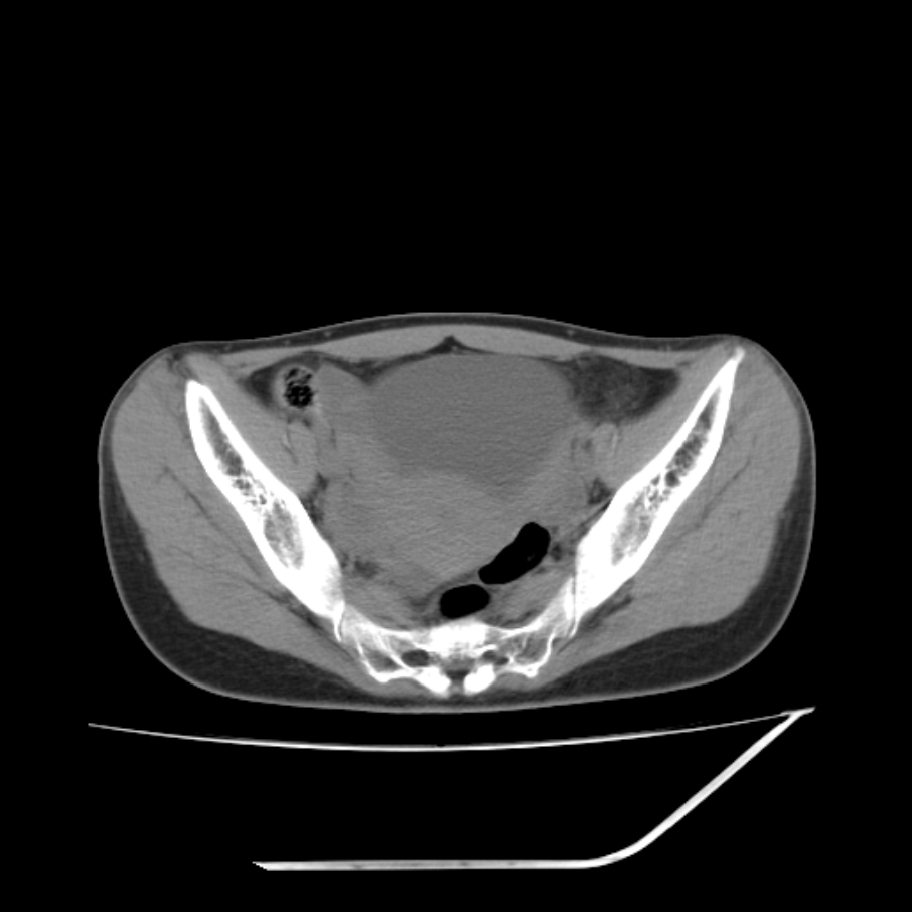

女,25岁。偶尔有右下腹不适感,余无明显异常。(结婚半年),囊壁较厚,是卵巢囊肿吗?

其上一层面见两枚小气泡影,考虑为肠管影可能,不完全除外囊肿

右侧卵巢区椭圆形囊性肿物,内壁光滑 无分隔。直肠子宫间隙内有少量积液征象。结合临床考虑卵巢巧克力囊肿,还要问问有没有痛经,本例ct怎么没有灌肠?要是灌肠或前一前口服造影剂,起码可以和肠管区别开

b超示:囊实性占位,畸胎瘤?临床有痛经。

考虑右侧卵巢囊性占位性病变(巧克力囊肿?),盆腔积液有不排除宫外孕可能,请结合临床和b超。

右侧卵巢囊伴盆腔少量积液。